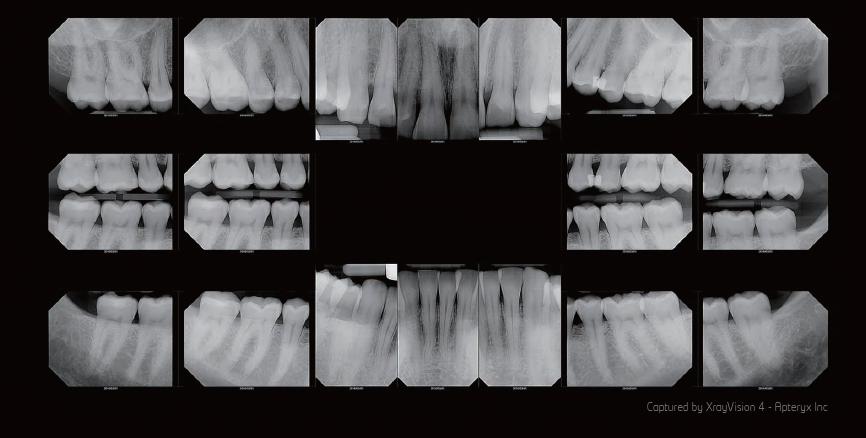

Imagen Intraoral

Digitalice su exámen intraoral con RIOsensor.

Agilice el flujo de trabajo con imágenes digitales de alta resolución.

Excelente sensor intraoral

Imágenes de alta resolución.